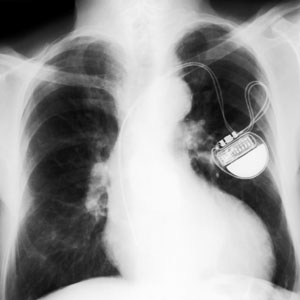

El marcapasos es un aparato implantado por debajo de la clavícula, a nivel subcutáneo, mediante una cirugía que no suele requerir anestesia general.

Consta de un generador y un cable (o más), el cual detecta si el corazón recibe el estímulo propio y, en caso contrario, es capaz de crearlo y mantener así una frecuencia cardíaca adecuada.

La implantación de un marcapasos conlleva un seguimiento clínico para asegurar que éste ejerce su función y que la batería, que dura entre 6 y 10 años, no está agotándose.

Las generaciones actuales de marcapasos suelen tener pocas interferencias, aunque se recomienda situar el móvil un poco alejado de la zona de implantación del marcapasos y evitar permanecer en zonas con campos electromagnéticos.